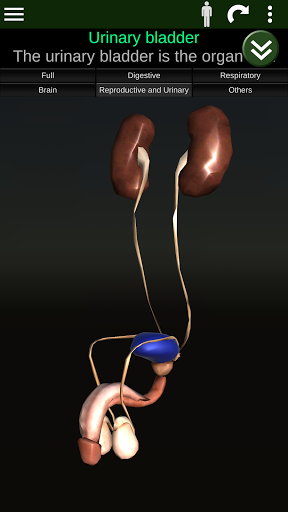

Menampilkan model anatomi 3D dari organ utama tubuh manusia dan penjelasannya masing-masing.

* Sistem reproduksi, yang meliputi organ reproduksi pria dan wanita.

* Mudah diakses dan dinavigasi (zoom, rotasi 3D).

* Deskripsi masing-masing organ.